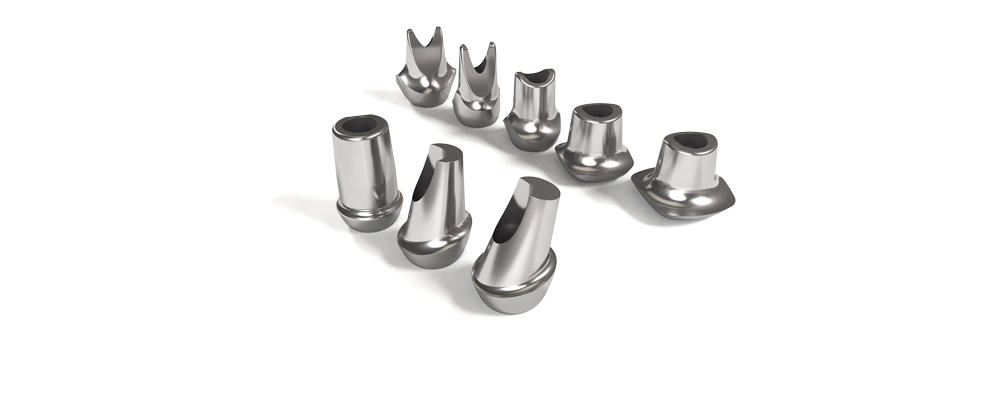

Le positionnement vertical de l’implant est légèrement modulable selon le biotype parodontal. L’interface prothétique est décalée au dessus du joint muqueux ; le risque de contamination iatrogène lors des phases de restauration prothétique est réduit.